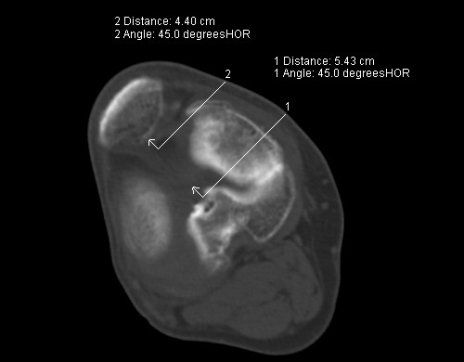

- Insertionstendinopathie der Achillessehne (Achillodynie): chronische Sehnenscheidenentzündung der Achillessehne mit eingeschränkten und schmerzhaften Bewegungen der Ferse oder des Sprunggelenkes möglicherweise entstanden nach Sportverletzungen oder Überbelastung des Sprunggelenkes.